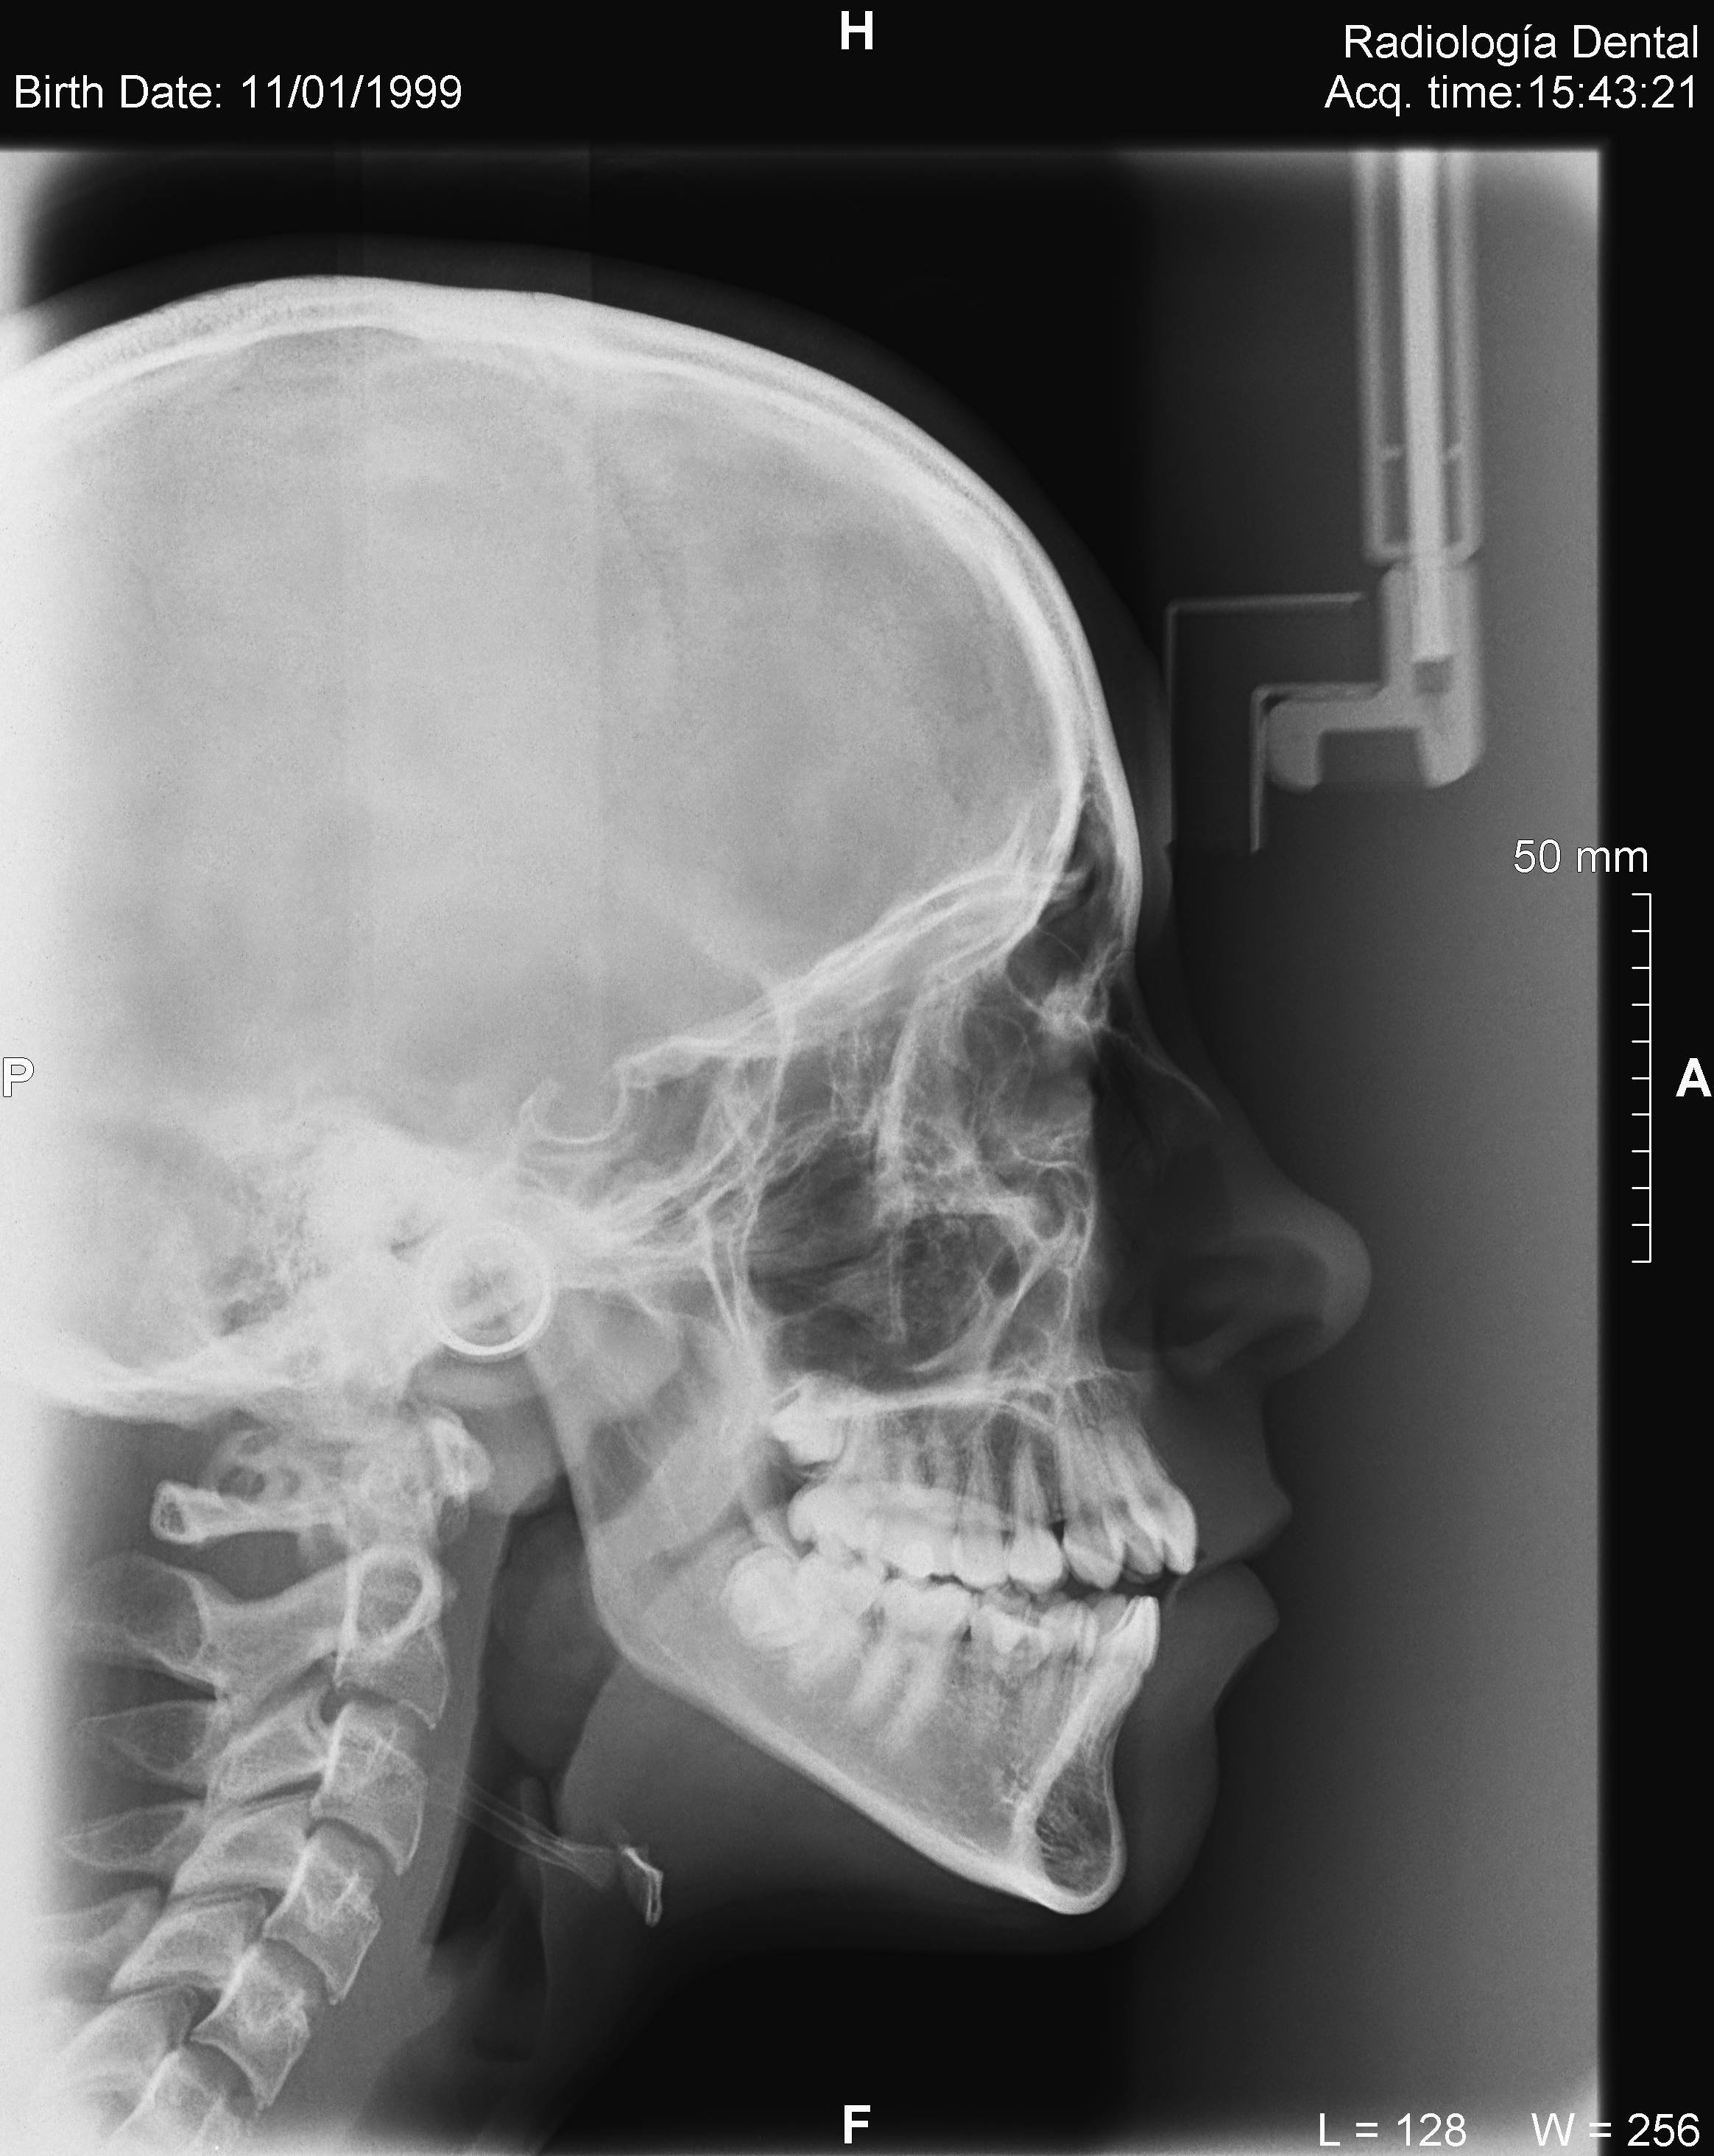

• Telerradiografía frontal y lateral digital

• Cefalometría computarizada

Algunos ejemplos de imágenes digitales

Pulse en las imágenes para ver la ampliación